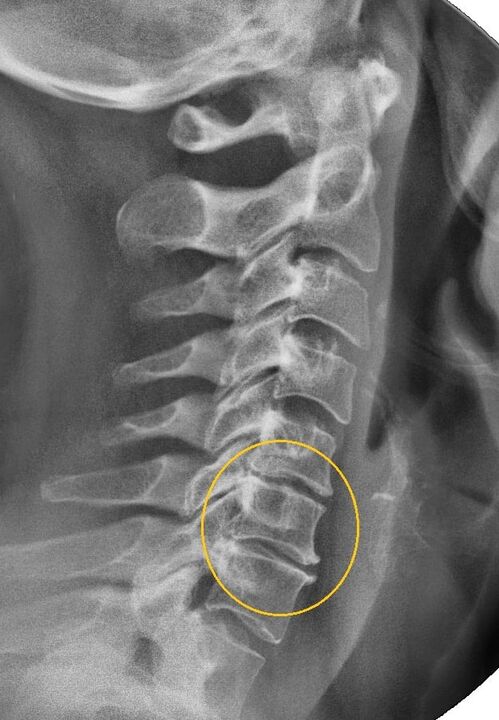

O procedemento diagnóstico máis informativo é a radiografía. As patoloxías de 1o grao corresponden á 1a ou 2a etapa radiolóxica. As imaxes resultantes visualizan sinais típicos de enfermidade.

| Etapas de raios X da osteocondrose cervical de 1º grao | Sinais característicos |

|---|---|

| Etapa 1 | Pequenos cambios na curvatura da columna vertebral na zona do pescozo, que afectan a un ou máis segmentos |

| Etapa 2 | Lixeiro engrosamento dos discos intervertebrais, deformación dos procesos uncinados, endereitamento da lordose, pequenos crecementos das estruturas óseas. |